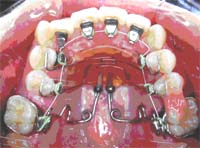

<リンガル矯正>

リンガル矯正( 歯の裏側に着ける矯正治療 )のセットアップと実際の装置です。

表からは見えないので、矯正装置が気になる方におすすめです。

この写真は、大臼歯を後方に移動して隙間を作りながら,歯の凸凹を治しております。